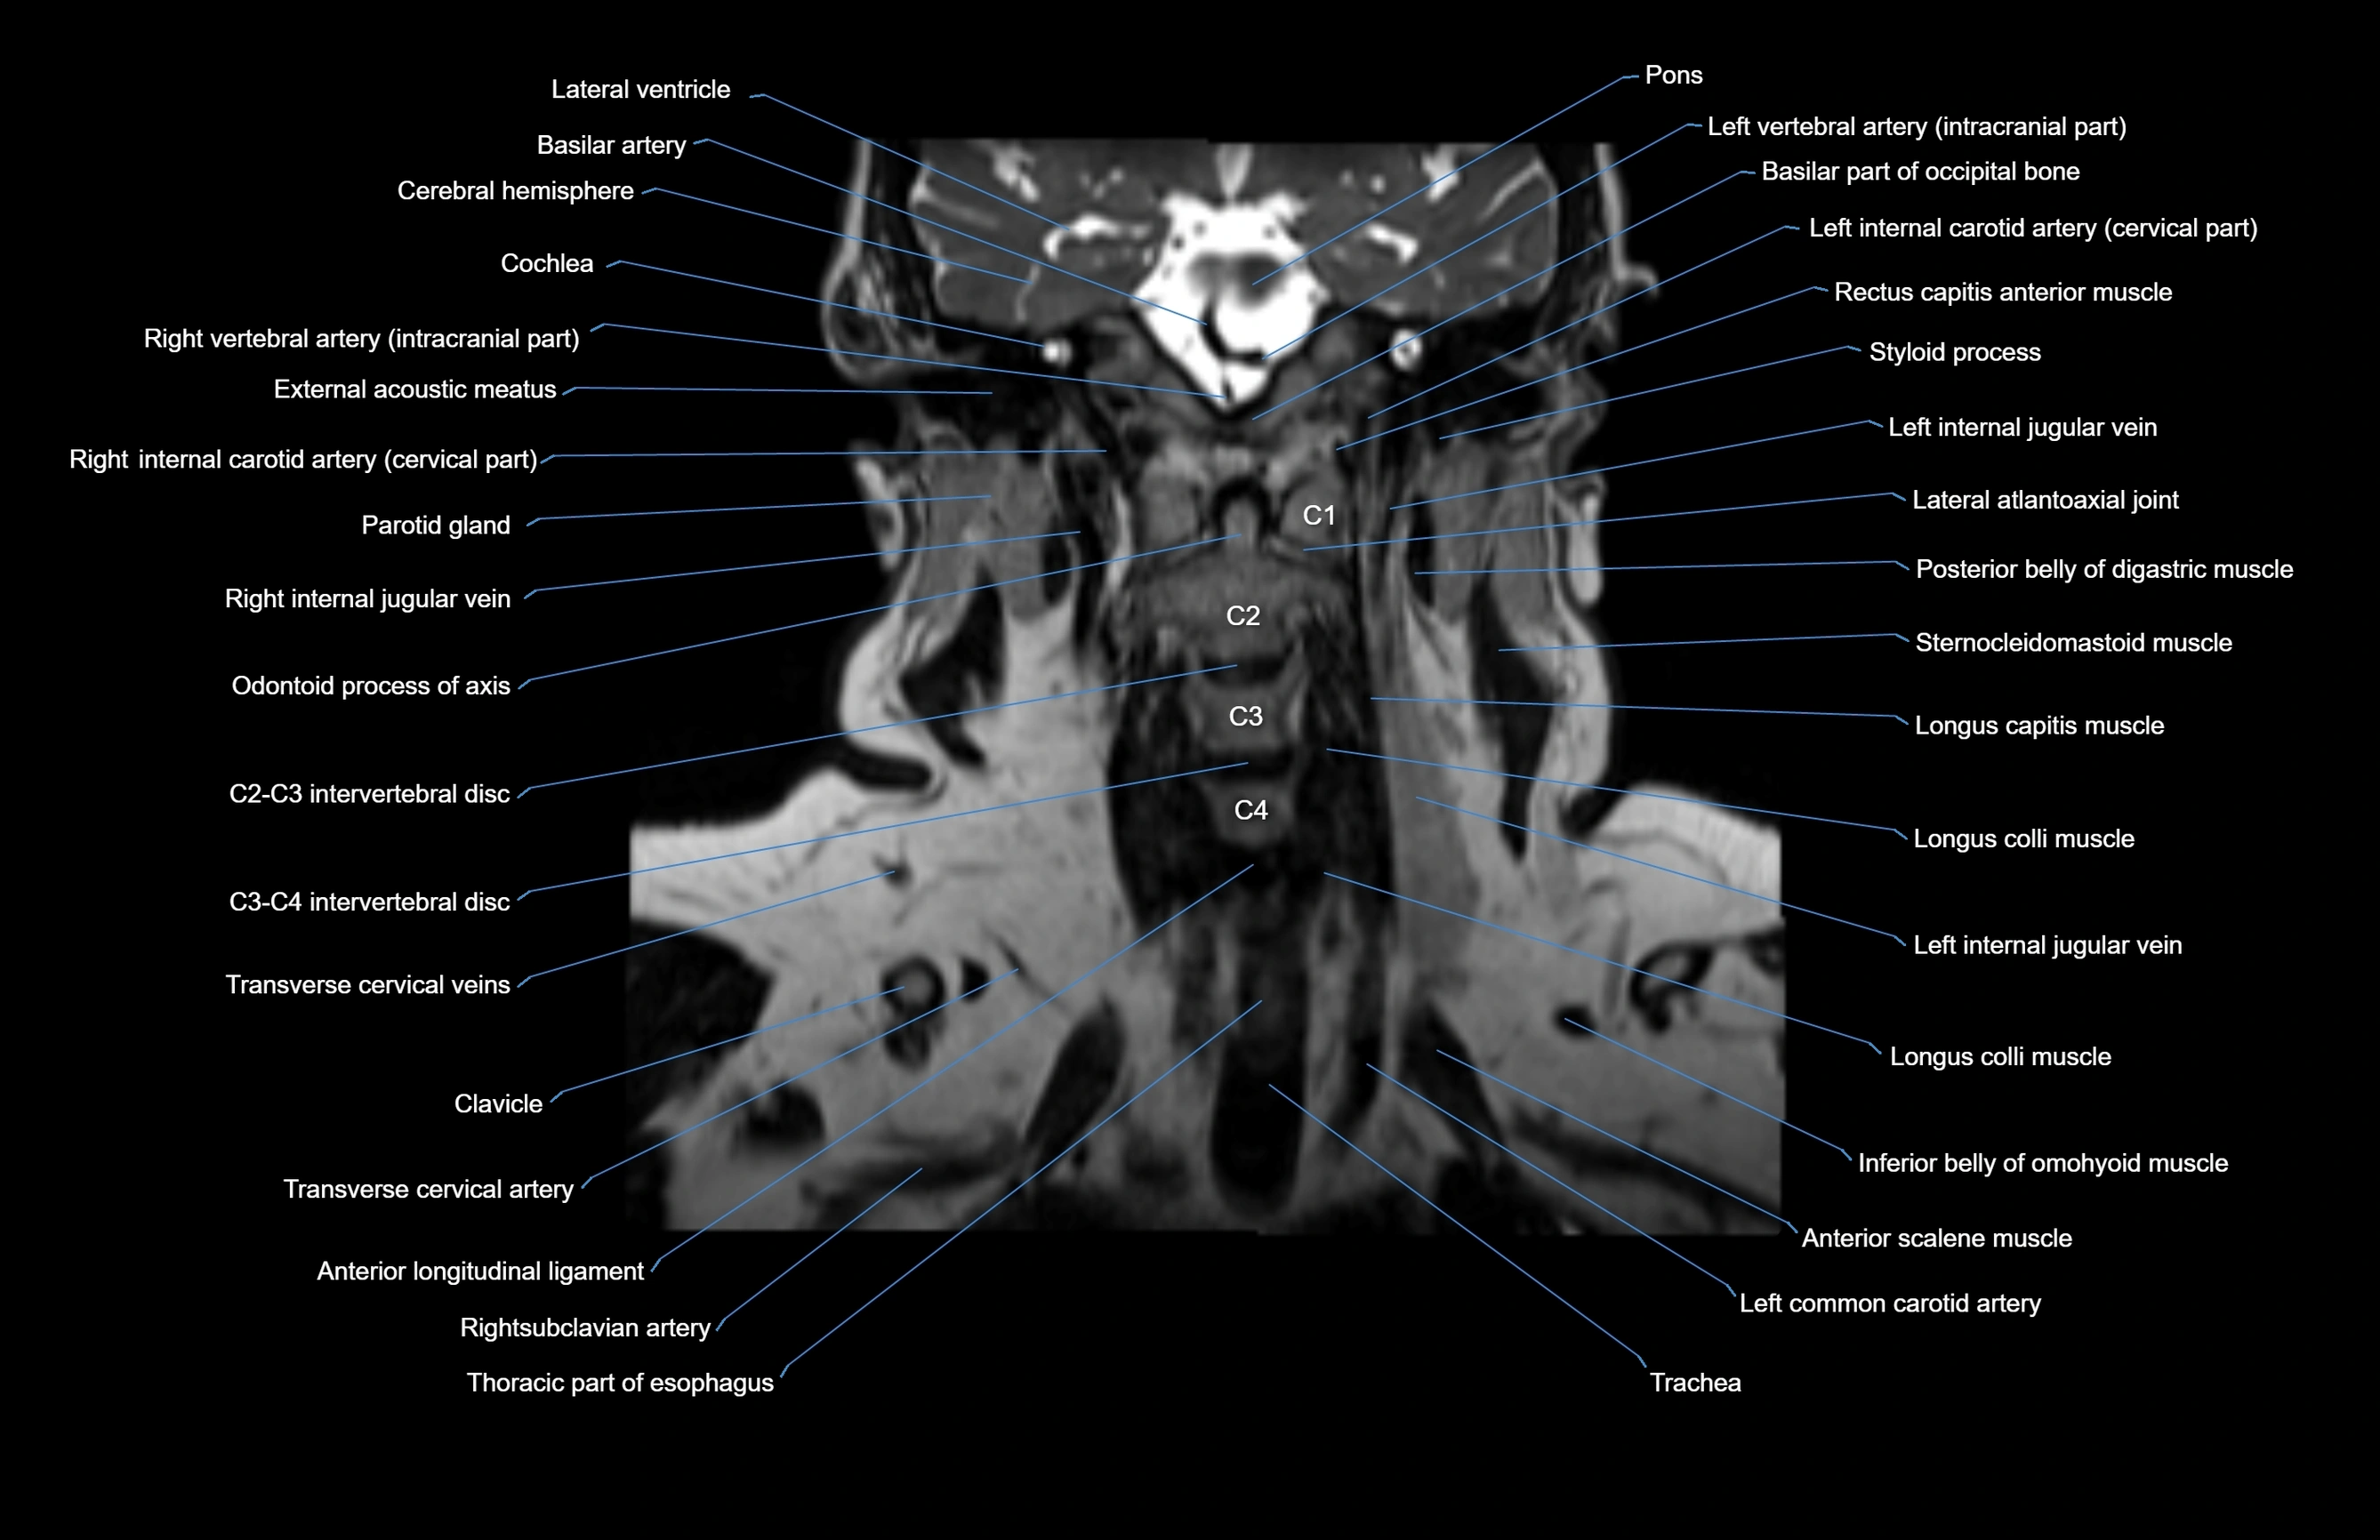

MRI images